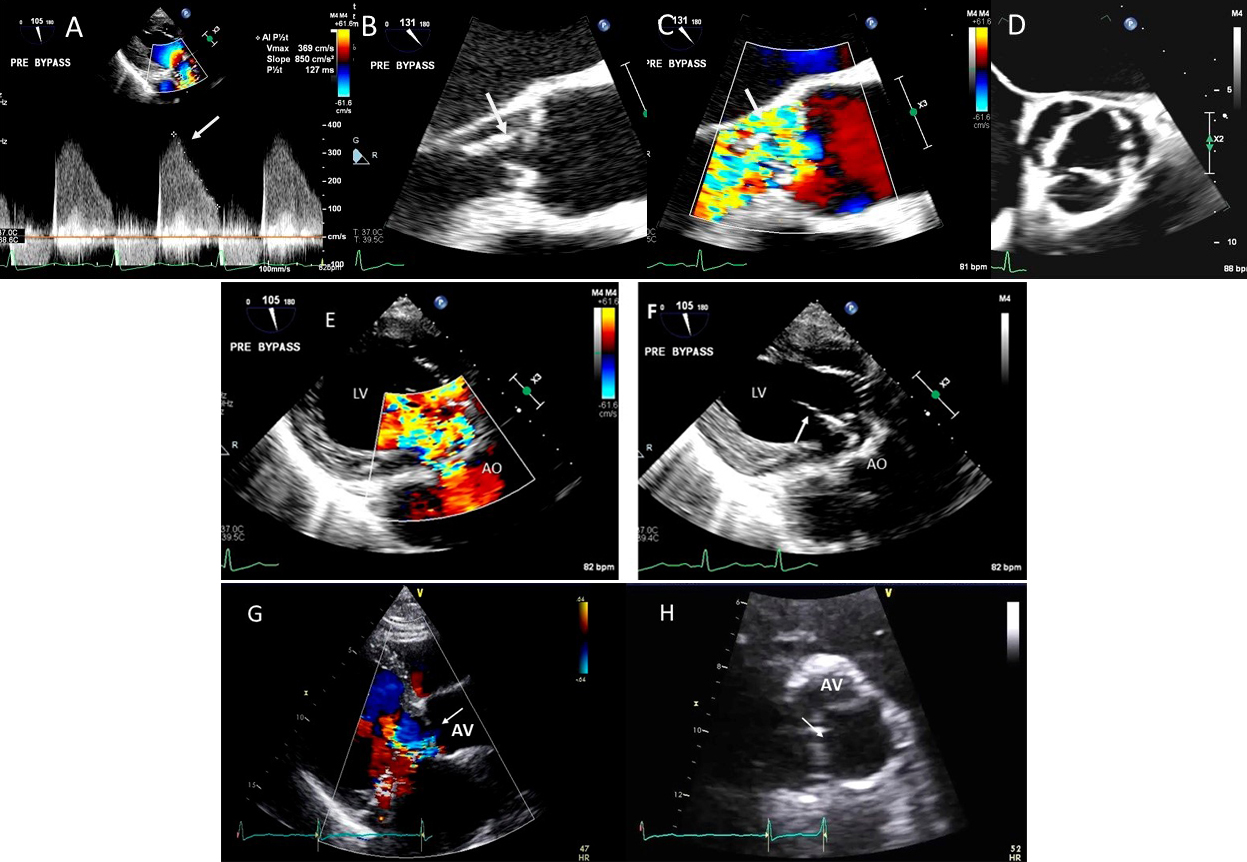

II Aortic cusp prolapse/perforation: endocarditis, aortic dissection (Figs. 8, 9)

Fig. 8.Aortic regurgitation and left coronary cusp perforation. (A) TTE color Doppler parasternal short axis view demonstrating left coronary cusp perforation (white arrows), resulting in aortic regurgitation. (B) TTE color Doppler short axis view showing origin of aortic regurgitation through the left coronary cusp perforation (white arrow). (C) TEE color Doppler short axis view showing a better delineation of the origin of aortic regurgitation jet through the left coronary cusp perforation (white arrow). (D) TEE long axis view demonstrating the perforated coronary cusp on 2D (white arrow) with aortic regurgitation jet originating through the perforation (white arrow) and not through the aortic leaflet coaptation. (E) 3-dimensional (3D) TEE short axis view of the aortic valve showed a clear definition of the left coronary cusp perforation (white arrow). (F) 3-D TEE color Doppler short axis view showing aortic regurgitation jet originating through the left coronary cusp (black arrowhead). Direct planimetry of color Doppler aortic regurgitant orifice can be performed online or via offline post processing of 3D data sets without geometrical assumptions of PISA method or continuity equation.

Common causes of leaflet malfunction causing AR include degenerative leaflet calcifications, and infective endocarditis (Fig. 10), bicuspid aortic valve perforation and rheumatic fever. The causes of AR include Marfan’s syndrome, annulo-aortic ectasia (idiopathic root dilatation) (Fig. 9), aortic dissection, connective tissue disease, and syphilis. The Carpentier classification is also widely used to describe the mechanism of AR [63].

Using 2D biplane, 3D and 3D color Doppler, the exact perpendicular plane to the aortic regurgitation jet can be identified, from which planimetry of the AV coaptation gap as well of the color Doppler vena contracta can be performed [64]. This has been shown to have a good correlation with aortographic grading of AR. When the shape of the regurgitant orifice is nonsymmetric, by using 3D images, invalid geometric assumptions of the vena contracta can be avoided with direct measurement [65]. 3D echocardiographic color Doppler also allows visualization, and measurement of multiple jets and correlated morphologically with surgical findings [65].

Isolated aortic valve perforation can occur post endocarditis or post cardiac surgery [15, 16, 17]. Restriction of aortic valve leaflet motion may occur due to leaflet tethering [18, 19]. Combined use of 2D, color Doppler and 3D TEE may facilitate location and mechanism of AR and can allow valve repair instead of replacement.